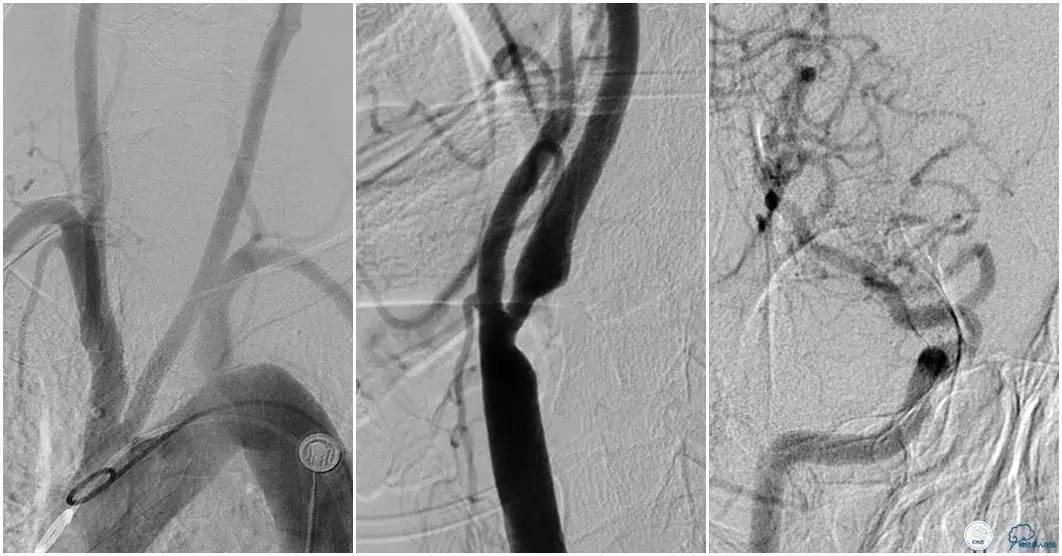

12:35穿刺成功,TOT 185min。3型主动脉弓,右侧颈内动脉起始部狭窄70%,右侧大脑前动脉A1段未显影。

双侧大脑前动脉A4段闭塞,右侧大脑前动脉由左侧大脑前动脉经前交通动脉代偿供血。

6F Envoy置于颈内动脉C3段,选用Solitaire-FR 4*20mm支架释放于右侧大脑前动脉,完全覆盖血栓。

6F Envoy置于左侧颈内动脉C3段,选用Solitaire-FR 4*20mm支架释放于右侧大脑前动脉取栓1次,血流达TICI 2b。

Solitaire-FR 4*20mm支架释放于左侧大脑前动脉取栓1次,取出少许血栓重复造影左侧大脑前动脉胼周动脉开口后,右侧大脑前动脉A2段以远未显影,考虑栓子逃逸。

选用Solitaire-FR 4*20mm支架分别于右侧大脑前动脉A2-A3段,左侧胼周动脉,右侧胼周动脉取栓3次。

双侧大脑前动脉完全显影,TICI 3级,TOR 261min。